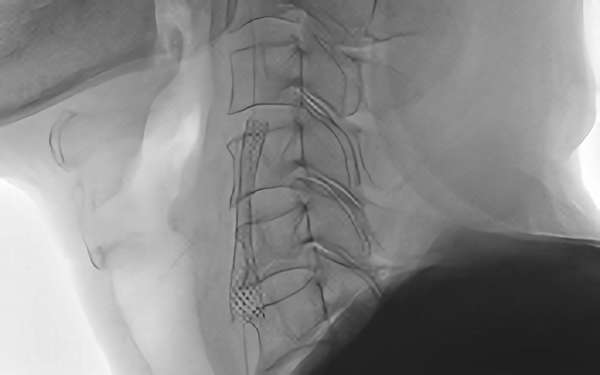

378

'19年1月30日

左内頚動脈狭窄症

70代

大阪府の病院

'19年1月